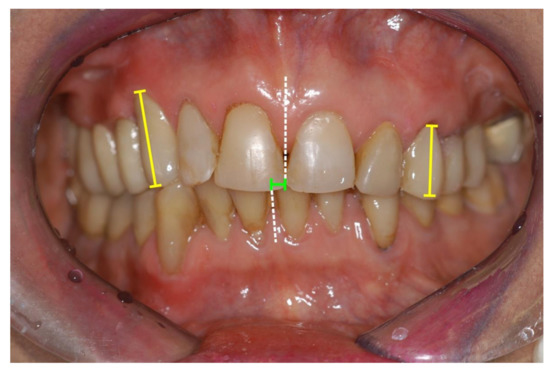

Unilateral mandibular condylar hyperplasia is a rare disease, where one condyle exhibits excessive growth [124,125,126]. A benign tumor of the long bones, osteochondroma, may also affect the mandibular condyle with similar consequences: Condylar growth leads to dislocation of the mandibular body in vertical and/or anterior direction. Asymmetry and occlusal imbalances are frequent consequences (Figure 10 and Figure 11). Treatment includes surgical remodeling or removal of the affected condyle and, if necessary, insertion of a neocondyle.

Figure 10.

Panoramic radiograph of a unilateral condylar hyperplasia on a 38-year-old female patient’s left side. Green dotted lines outline the condyles; arrows indicate non-occlusion in the left bicuspid and molar region. In this case, the panoramic radiograph gives an impression of asymmetry. However, CT and cone beam CT are superior in accuracy.

Figure 11.

Intraoral view of the same patient. Unilateral open bite on the left side and moderate mandibular midline shift are clearly visible. At present, occlusal stability is maintained by an intraoral splint until a definite correction with crowns and overlays in the left mandible will be performed.